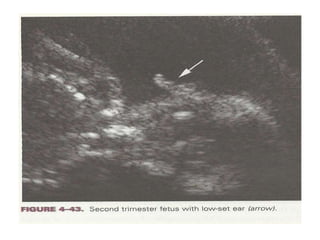

Ear Length

taken as one of the soft markers of aneuploidy.

• Sensitivity of short ear length (<10th percentile of GA)

in midtrimester is 71%. ( as per Lettieri et al).

• Measured to expected ear length ratio < 0.8 had

sensitivity of 75% for downs and 83.3% for trisomy 18.

(Callens 5th edi)

• Further studies has shown that sensitivity of ear length

for downs syndrome is 41%, for trisomy 18 is 96% and

for trisomy 13 its 100%.